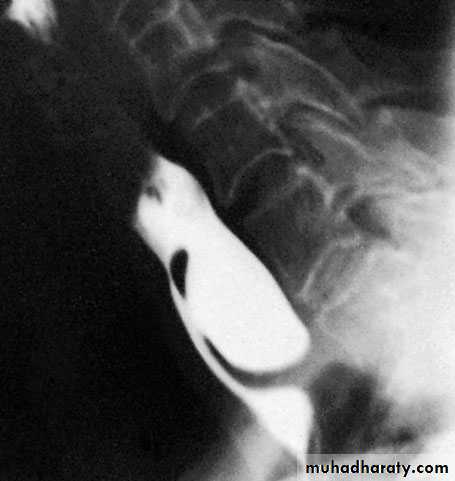

Zenker’s diverticulum (Pharyngeal pouch)

it protrudes posteriorly above the

cricopharyngeal sphincter through the natural weak point (the

dehiscence of Killian) between the oblique and horizontal

(cricopharyngeus) fibres of the inferior pharyngeal constrictor

Barium swallow